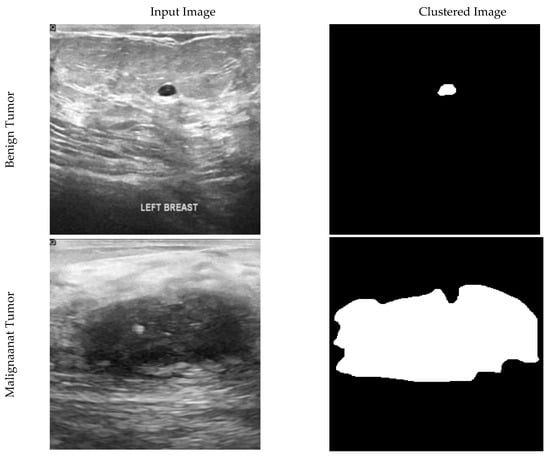

In this paper, segmentation of images has been used to find the primary location of the tumor. Segmentation is not one of the main steps of the convolution and DL algorithm. It has been used to validate the results. By separating pixels with zero values as the background, each non-zero pixel is the mass breast threshold (225). Each remaining pixel is 127 to the normal breast tissue, as shown in Figure 1.

Ultrasound and clustered images of breast cancer for benign, malignant, and normal tissue conditions.